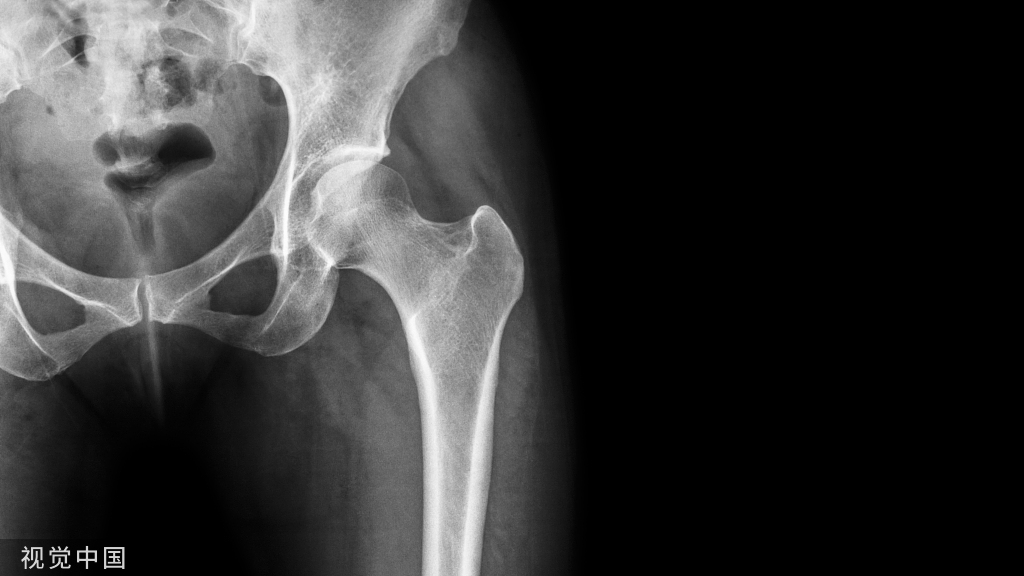

影像学表现

一、X线

1.早期表现为局部软组织肿胀,髌韧带增粗肥厚显著,继之则产生肌腱的钙化和骨化,胫骨结节呈舌状隆突,密度增高、碎裂,且与骨干轻度分离,形成大小、形态不一的骨碎块。

2.分离部位的骨骺边缘可见小的裂隙状缺损。

3.骨骺修复后胫骨结节可恢复正常或略有增高隆起,但常可留下分离的碎骨块,至成年时为胫骨结节上方的游离体,长期游离于髌韧带内。

男,11岁,胫骨前结节稍肿胀,右膝疼痛两月余,按压疼痛,胫骨结节下部与骨干分离。

X线片可显示胫骨结节骨软骨炎患者骨质及软组织的异常改变,是诊断胫骨结节骨软骨炎颇有价值的方法,对一些早期及可疑患者可进一步做CT或MRI检査